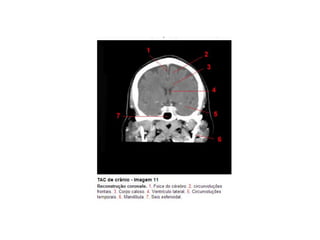

Anatomia E Protocolo Tomografia Computadorizada de Crânio PPT